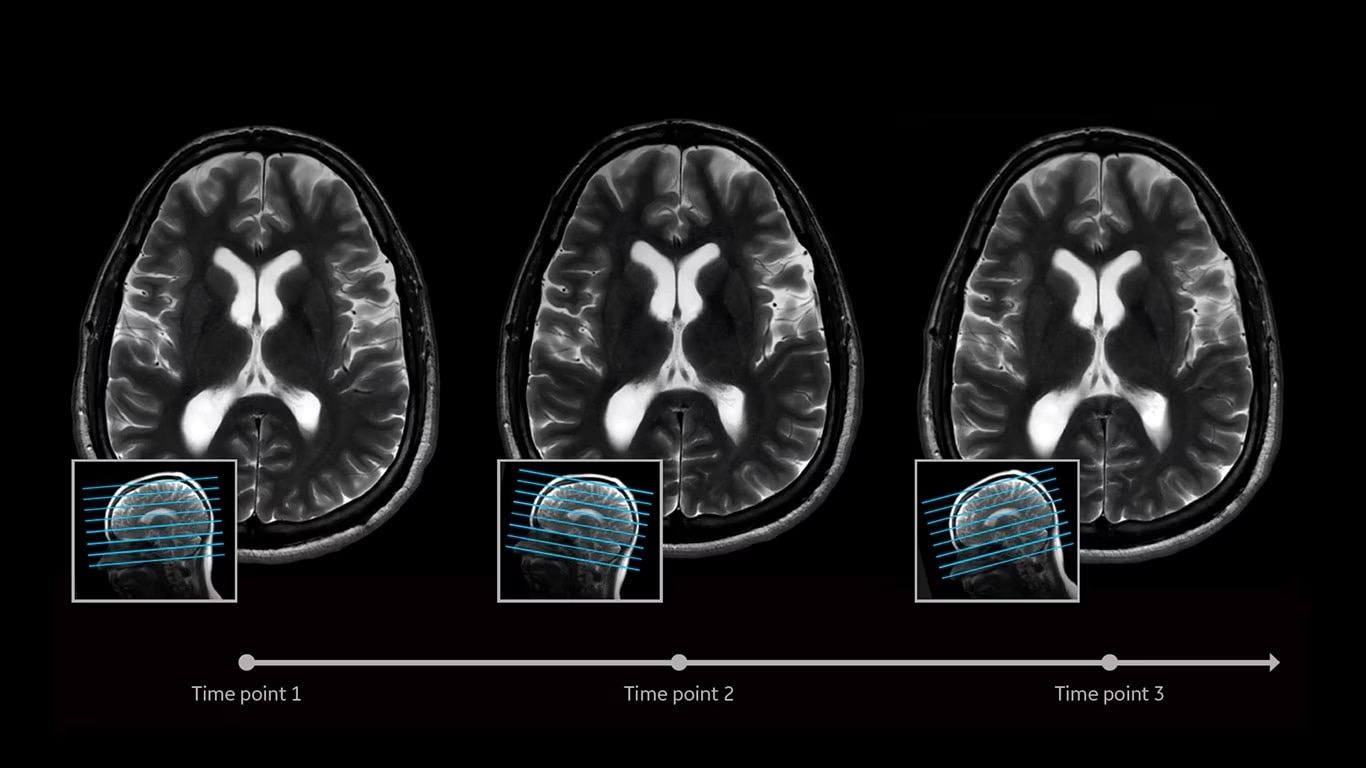

AIR x™ automatically detects patient anatomy and prescribes MRI slices

Eliminate the sources of variation by letting processes flow. AIR x™ uses deep-learning algorithms created from a database of 10's of thousands of images to automatically detect patient anatomy and prescribe MRI slices for routine and challenging neurological and knee exams, delivering consistent and quantifiable results. The automated workflow creates efficiency and reproduces steps used in planning to ensure exam consistency for same patient follow-up.

Automated MRI slice placement

Determine the best MRI slice placement

AIR x™ automatically detects patient anatomy and prescribes MRI slices for routine and challenging neurological and knee exams, delivering consistent and quantifiable results.

Consistent and accurate images

Deliver consistent results

Deliver consistent MRI slice placements across multiple clinical time points, with a deep-learning algorithm that provides efficiency and time savings.